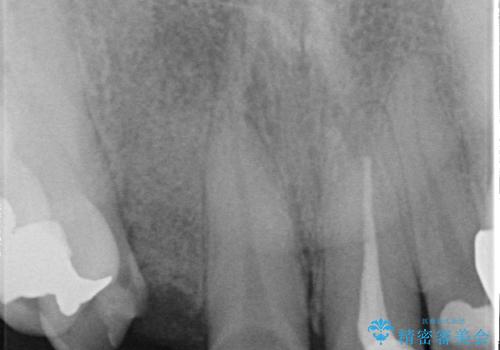

診査の結果右上2は歯根が破折しており、それが原因で骨及び歯肉の吸収が起きていました。

このまま右上2の抜歯を行うとさらに歯茎が下がる恐れがあったため、歯の挺出によって骨レベルを回復した上で抜歯し、歯槽堤保存術(抜歯窩に人工骨を填入する手術)を行いました。

その後ブリッジによる補綴を行うことで、自然な見た目を再現することができました。